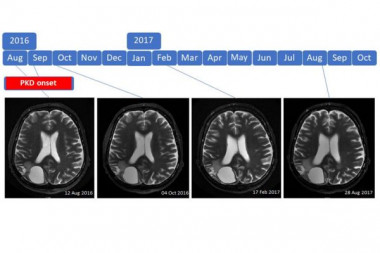

Treatment of high-grade brain tumor using the paleolithic ketogenic diet (PKD): Three case

Introduction: Prognosis for patients with high-grade brain tumor is poor and survival did neither substantially change with advances in chemotherapy, radiotherapy and molecular profiling. Ketogenic diets have been suggested as a promising alternative therapy.